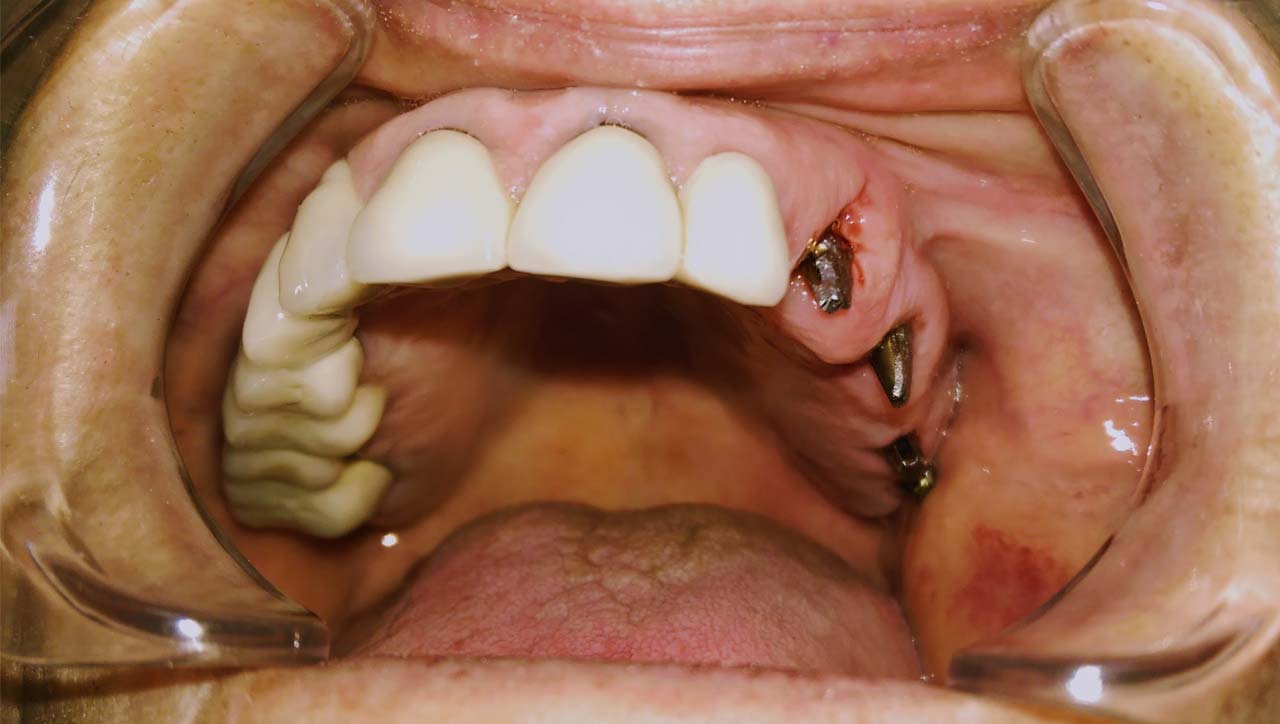

Implantáció törött, rossz fogak helyett

A rossz fogakat és a mozgó, törött fogakon álló hidat a fogakkal együtt eltávolítottuk. A fogak helyére, és a stratégiailag jó csontállományú területekbe azonnal behelyezett implantátumokra 3 nap múlva elkészítettük az esztétikus, rögtön terhelhető ideiglenes hidat.